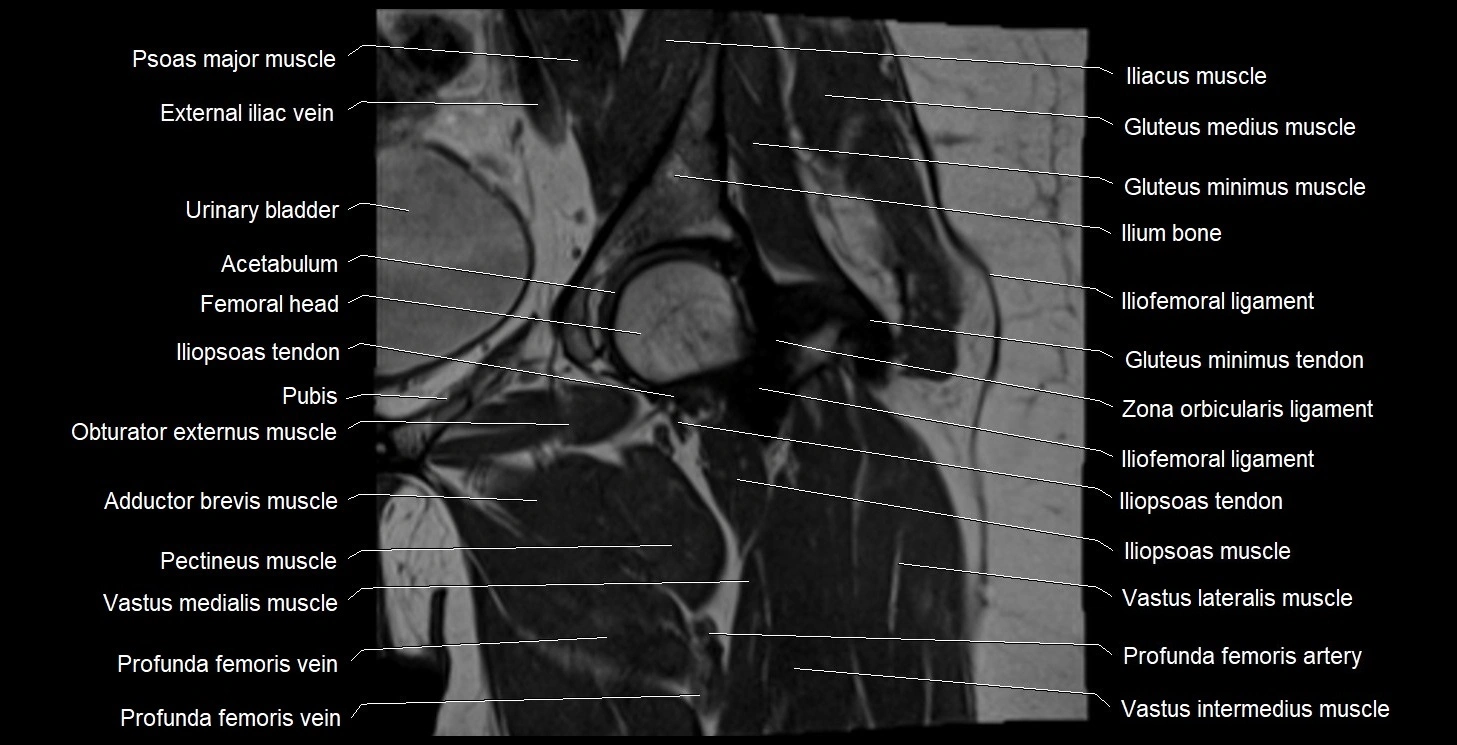

- Acetabulum

- Head of femur

- Hip joint

- Iliopsoas muscle

- Iliopsoas tendon

- Ilium bone

- Obturator externus muscle

- Pectineus muscle

- Psoas major muscle

- Urinary bladder

- Vastus intermedius muscle

- Vastus lateralis muscle

- Vastus medialis muscle